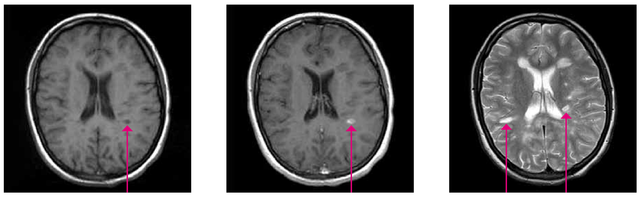

Kernspinaufnahmen mit der T1-Sequenz

Hier erscheint alles grau und schwarz. T1-Sequenzen sind gut geeignet, um bleibende Gewebeschäden zu erkennen. Im Marklager finden sich meist rundliche Flecken. Dabei ist wichtig zu beachten, dass unterschiedliche Graustufen das unterschiedliche Ausmaß der Gewebeschädigung widerspiegeln. Diese Flecken werden „hypointens“ genannt (hypo = unter, niedrig). Auch diese Hypointensitäten bilden sich teilweise wieder zurück. Nur ein kleiner Teil wird zu bleibenden „schwarzen Löchern“ als Ausdruck bleibenden Gewebeschadens. In T1 lässt sich ferner das Schrumpfen des Gehirns über die Zeit, das bei MS-Betroffenen schneller voranschreiten kann als bei Gesunden am besten analysieren.

Kontrastmittel-verstärkte T1-Bilder

Oft erfolgt eine Kontrastmittelgabe über eine Vene im Arm. Das Kontrastmittel, z.B. Gadolineum, gelangt an Stellen in das Gehirn, an denen die Barriere zwischen Blut und Gehirn gestört ist. Dies lässt sich im T1-Bild als weißer Fleck identifizieren. Diese Störungen der so genannten Blut-Hirn-Schranke sind Ausdruck frischer entzündlicher Krankheitsaktivität. Kortison kann diese Störung gut unterdrücken. Deshalb ist eine Kontrastmittelgabe innerhalb der ersten vier Wochen nach einer Kortisontherapie meist nicht sinnvoll.

Kernspinaufnahmen mit der T2- oder FLAIR-Sequenz

Bei diesen Darstellungen können Entzündungsherde am besten entdeckt werden. Diese erscheinen im Bild jeweils hell oder „hyperintens“. Das Nervenwasser erscheint weiß in T2 und schwarz im FLAIR. Da bei MS die Veränderungen oft dicht an den Ventrikeln liegen, ist die FLAIR-Sequenz am besten geeignet, diese Entzündungsherde zu zeigen. Diese Herde können kommen und gehen. Viele sind im Verlauf nicht mehr nachweisbar.

Abb. 14, 15, 16: "Schwarzes Loch" in T1 (links), Kontrastmittelanreicherung in T1 (Mitte), Entzündungsherde in T2 (rechts)